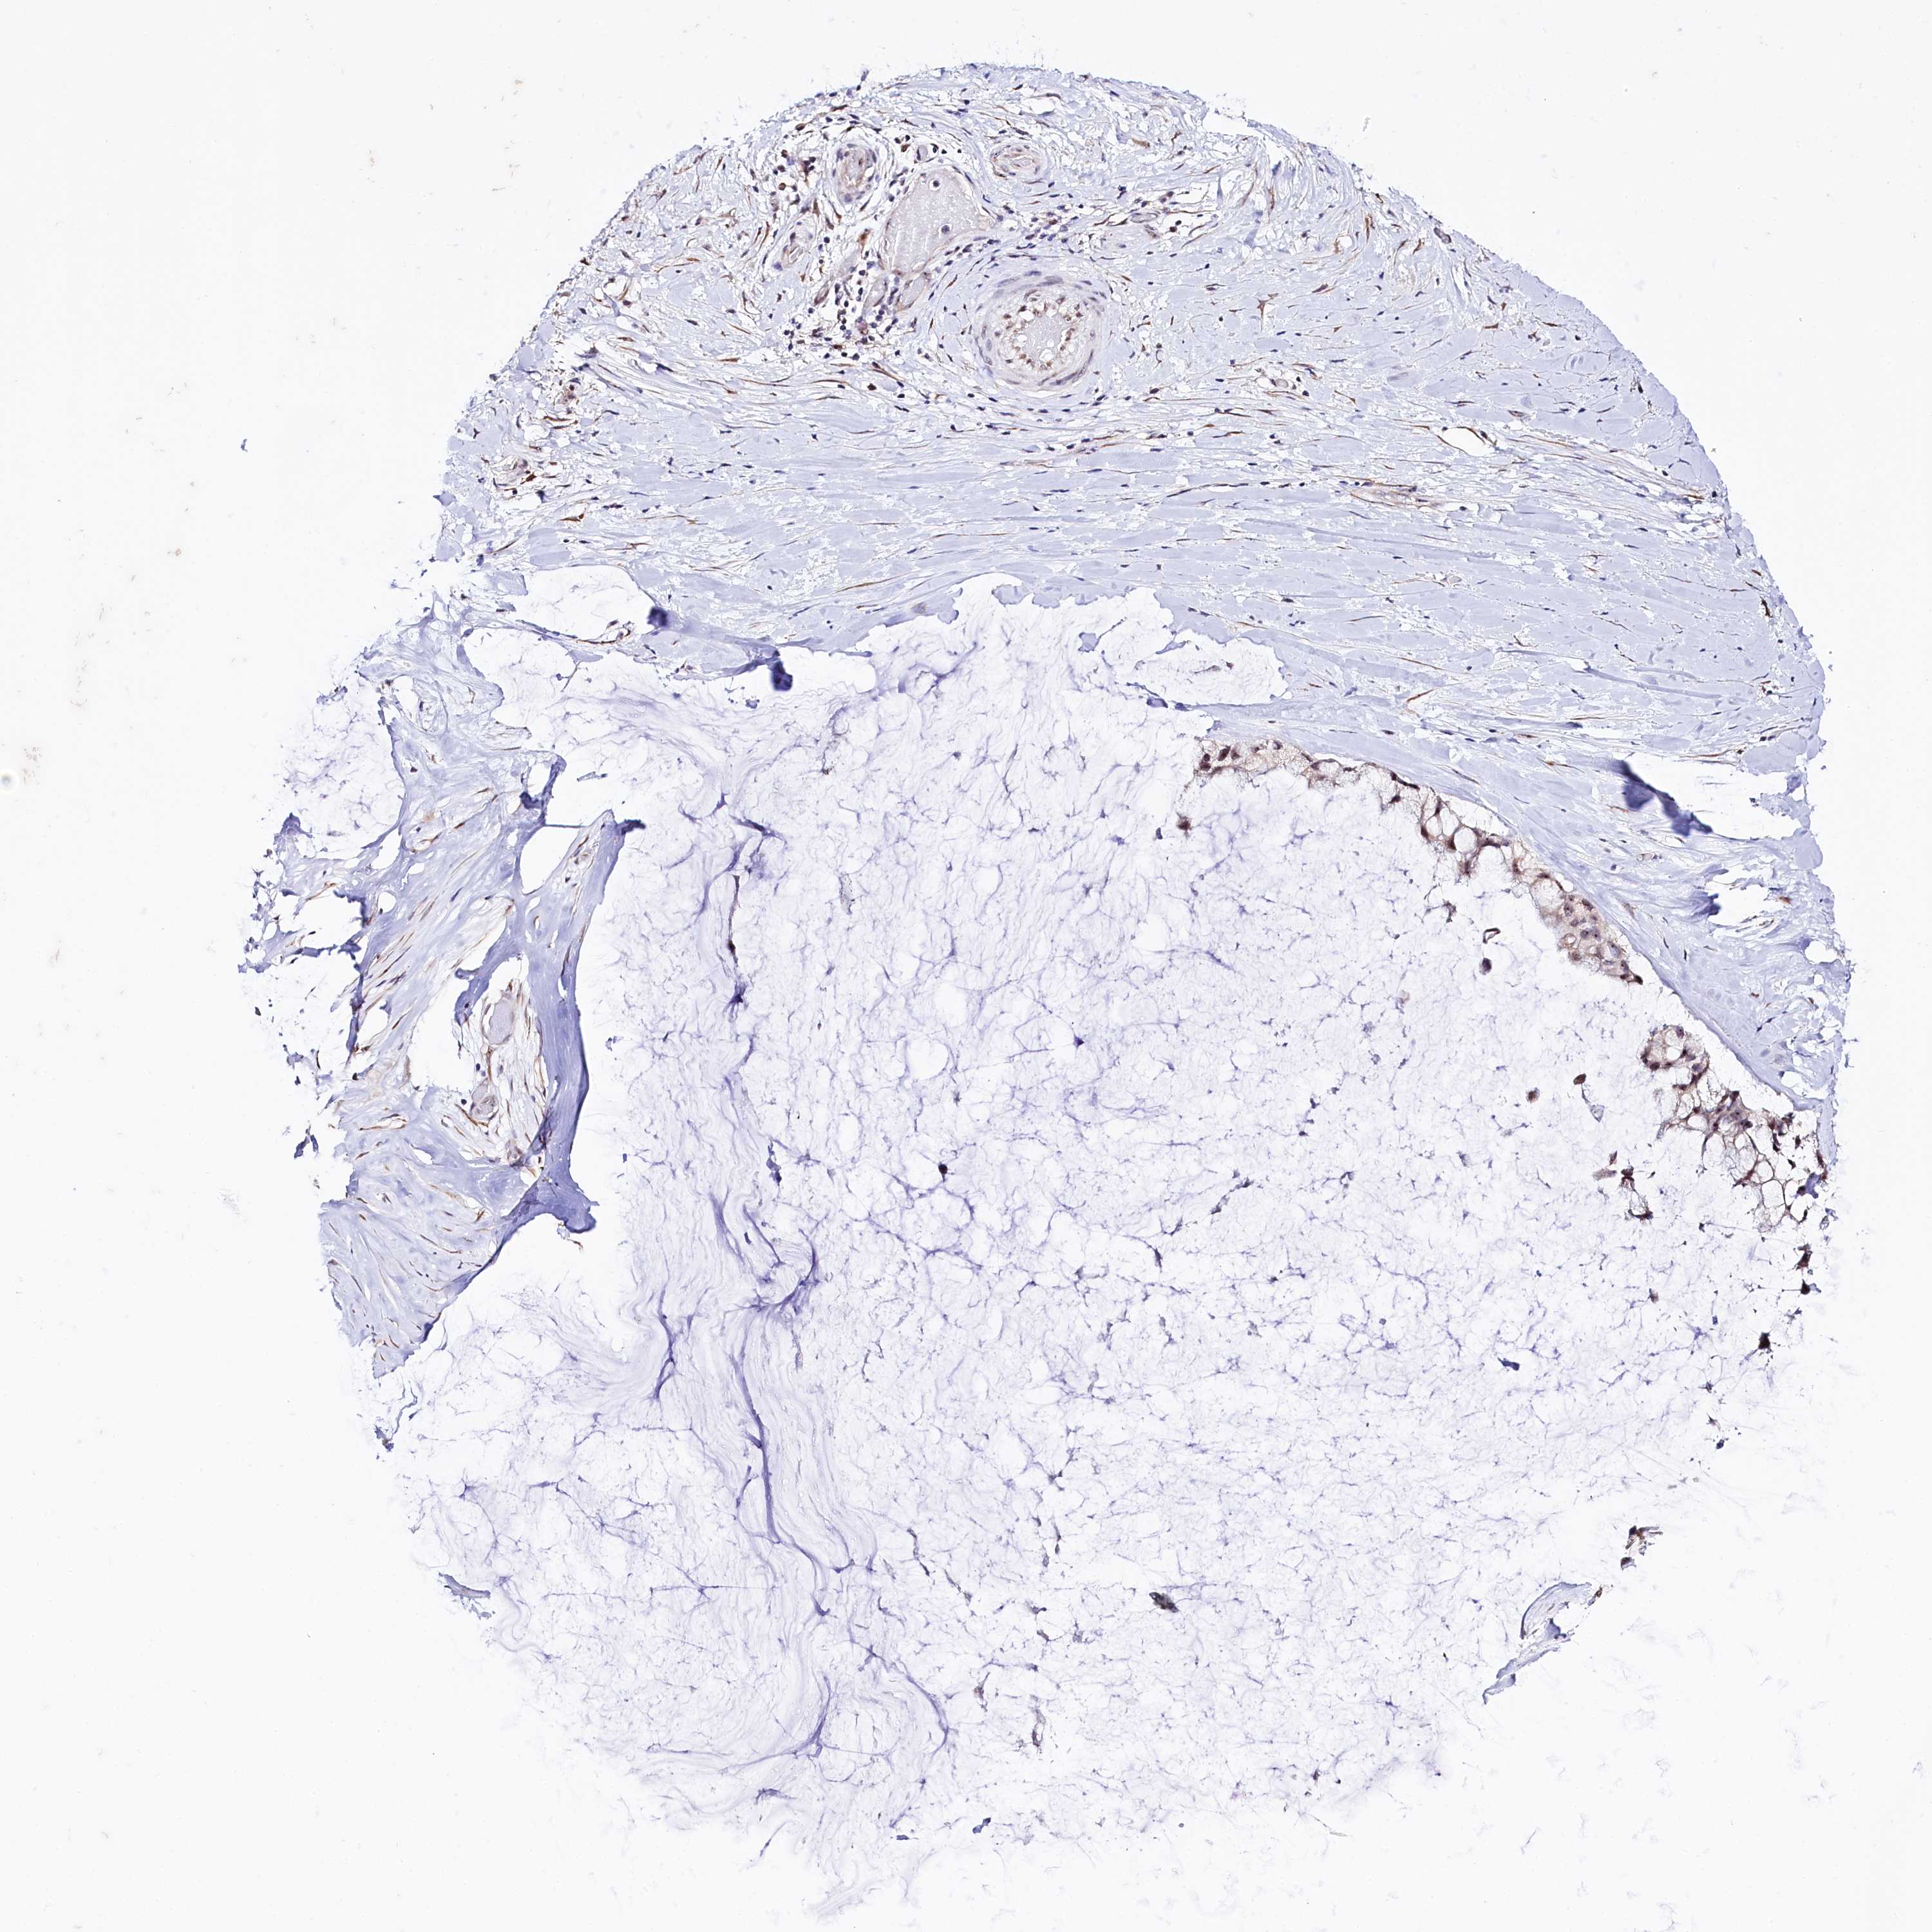

OVARIAN CANCER - Protein expressioni

A mouse-over function shows sample information and annotation data. Click on an image to view it in a full screen mode. Samples can be filtered based on level of antibody staining by selecting one or several of the following categories: high, medium, low and not detected. The assay and annotation is described here.

Note that samples used for immunohistochemistry by the Human Protein Atlas do not correspond to samples in the TCGA dataset.

Antibody stainingi

Antibody staining in the annotated cell types in the current human tissue is reported as not detected, low, medium, or high, based on conventional immunohistochemistry profiling in selected tissues. This score is based on the combination of the staining intensity and fraction of stained cells.

Each image is clickable and will lead to virtual microscopy that enables deeper exploration of all samples and also displays staining intensity scores, fraction scores and subcellular localization as well as patient and tissue information for each sample.

Antibody HPA038860

Staining

High

Medium

Low

Not detected

Intensity

Strong

Moderate

Weak

Negative

Quantity

>75%

75%-25%

<25%

None

Location

Nuclear

Cytoplasmic/membranous

Cytoplasmic/membranous,nuclear

Cystadenocarcinoma, serous, NOS

Carcinoma, endometroid

Cystadenocarcinoma, mucinous, NOS

Carcinoma, NOS